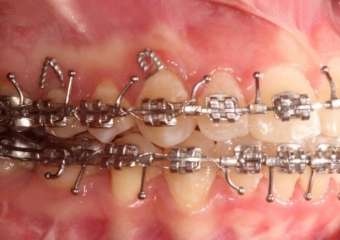

Mordida inicial

Mordida após a cirurgia